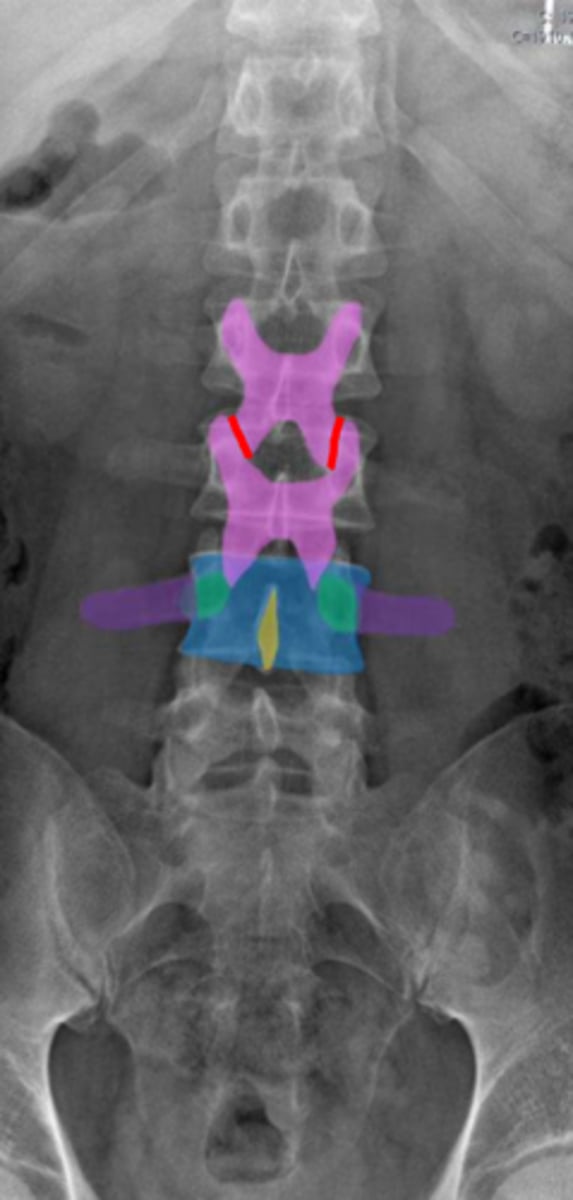

pedicles

Identify the green structure

spondylolysis

pars interarticularis

oblique view

What condition is being examined for in this radiograph?

What structure is it looking for?

What view is this radiograph in?